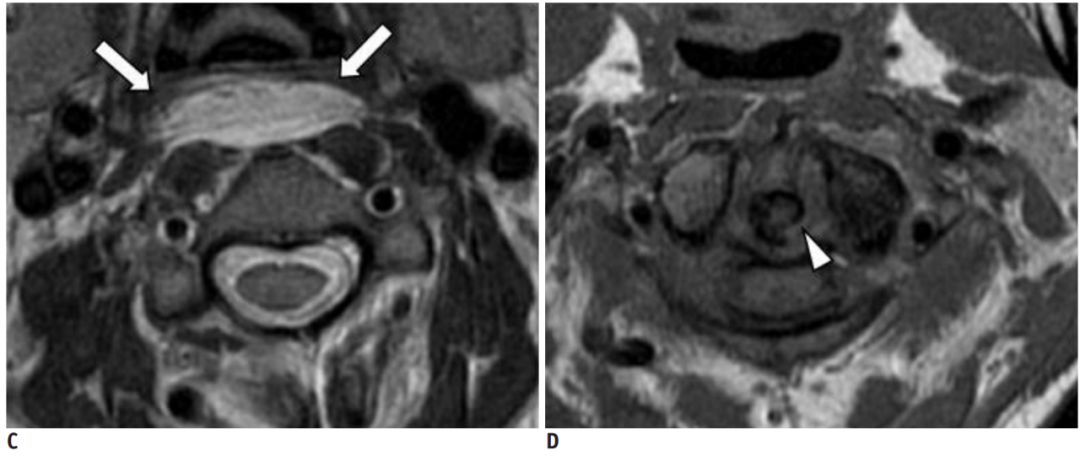

CT的高分辨率能够明确肌腱内的钙化,能够明确是钙化而不是其他骨骼来源的高密度影。钙化一般位于寰椎前弓的下方和枢椎齿状突的前方,少部分可位于下颈椎前侧。CT有助于明确椎体前积液的存在和排除其他病理表现,如骨折或脓肿。MRI对诊断不是必须,但有时可帮助确定软组织异常,排除咽后脓肿,脊椎炎或肿瘤。MRI检查T2加权在椎前可见局限性的裂隙样区域,大多位于C1-4水平,呈高信号改变,这反应是由于炎症引起的积液。T2加权、脂肪抑制序列和T1加权对鉴别积液和脂肪组织、含脂肪的骨髓以及咽后感染、脊椎炎有重要作用。MRI检查在钙化检查方面存在不足,T2加权呈低信号。

典型病例介绍

36岁女性,急性颈痛、吞咽困难伴颈部僵硬,MRI示C1-2前部颈长肌增厚呈低信号,提示钙化(长箭头)和C1-4椎前积液(无线箭头),经类固醇和止痛药治疗8天后症状消失,复查MRI提示上述表现消失。(PMID: 18765656)

C1-2前侧低信号(无线箭头)和C1-5椎前水肿(长箭头) (PMID: 19567634)

30岁女性,诊断为颈长肌钙化性肌腱炎,但钙化位于不寻常的位置:C4-5椎间隙前侧。A:颈椎侧位片示寰枢椎半脱位(长箭头)和椎前软组织肿胀(无线箭头);B,C和D:颈椎MRI示C1-6椎前软组织肿胀伴积液,D示齿状突骨侵蚀(无线箭头)

上述病人,E为增强,F为抑制像,G和H:经非甾体抗炎药治疗3天后查颈椎CT示C4-5椎前无定形钙化。

上述病人,I和J: 入院4天后复查颈椎MRI示椎前积液明显减少; K,随访2个月复查CT示C4-5前钙化灶减小。(PMID: 21852912)